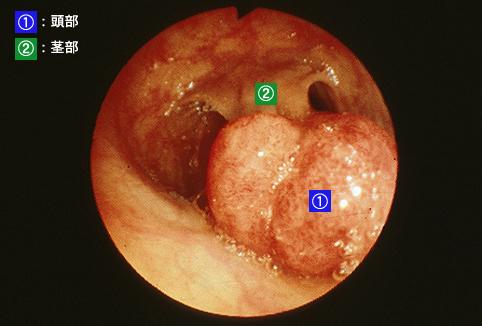

疾病(病理主体)的分类良性上皮性肿瘤/腺瘤

部位(按器官分)大肠/乙状结肠

检查方法内窥镜

肿瘤的肉眼分类0型(表在型)/I型(Ip)

肿瘤最大直径25~29